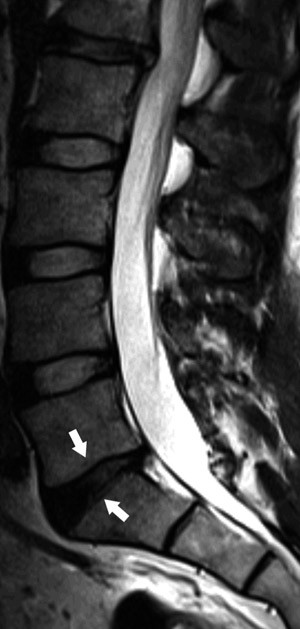

Mellomvirvelskivene består av en indre nucleus pulposus, som er en geléliknende støtpute av vann og proteoglykaner, samt en ytre anulus fibrosus, som består av tettpakkede fibre. Med alderen reduseres mengden vann i nucleus pulposus, og gradvis blir skiven mer fibrøs og uten noe klart skille mellom nucleus og annulus (11). Disse endringene kan fremstilles på MR. Hos barn og unge har en normal mellomvirvelskive høyt signal på T2-vektede bilder som tegn på høyt væskeinnhold, men allerede ved 30 års alder blir skiven normalt gradvis mørkere på grunn av at innholdet av væske har minsket (fig 1). Signalintensiteten i skivene er klart korrelert til alder, 90 % av asymptomatiske 60-åringer vil ha slike signalforandringer i skivene (11, 12). Det er ikke vist noen sikker og klinisk viktig sammenheng mellom forekomsten av slike degenerative skiveforandringer og pasientens symptomer verken i nakke eller i rygg (13, 14). Disse skiveforandringene må altså oppfattes som del av den normale aldringen.

Annulusrupturer er konsentriske eller radiære sprekker i anulus fibrosus. De ses på T2-vektede MR-bilder som områder med høyt signal i kanten av skiven (high intensity zone, HIZ), typisk i midtlinjen inn mot spinalkanalen i de nederste lumbale skivene (fig 2). Det har vært hevdet at annulusruptur kan gi ryggsmerter gjennom enten direkte mekanisk påvirkning av smerteførende fibre i kanten av skiven eller ved lekkasje av inflammatorisk aktive substanser fra nucleus pulposus (13). Imidlertid er dette et hyppig funn også hos asymptomatiske personer. I en normalpopulasjon av 40-åringer i Danmark (15) hadde ca. 40 % annulusruptur, og det var bare en moderat assosiasjon med kroniske ryggsmerter. Funn av slike rupturer på MR-bilder må ses som en del av utviklingen av skivedegenerasjon, men funnet i seg selv kan ikke tillegges noen vesentlig betydning som årsak til symptomer.